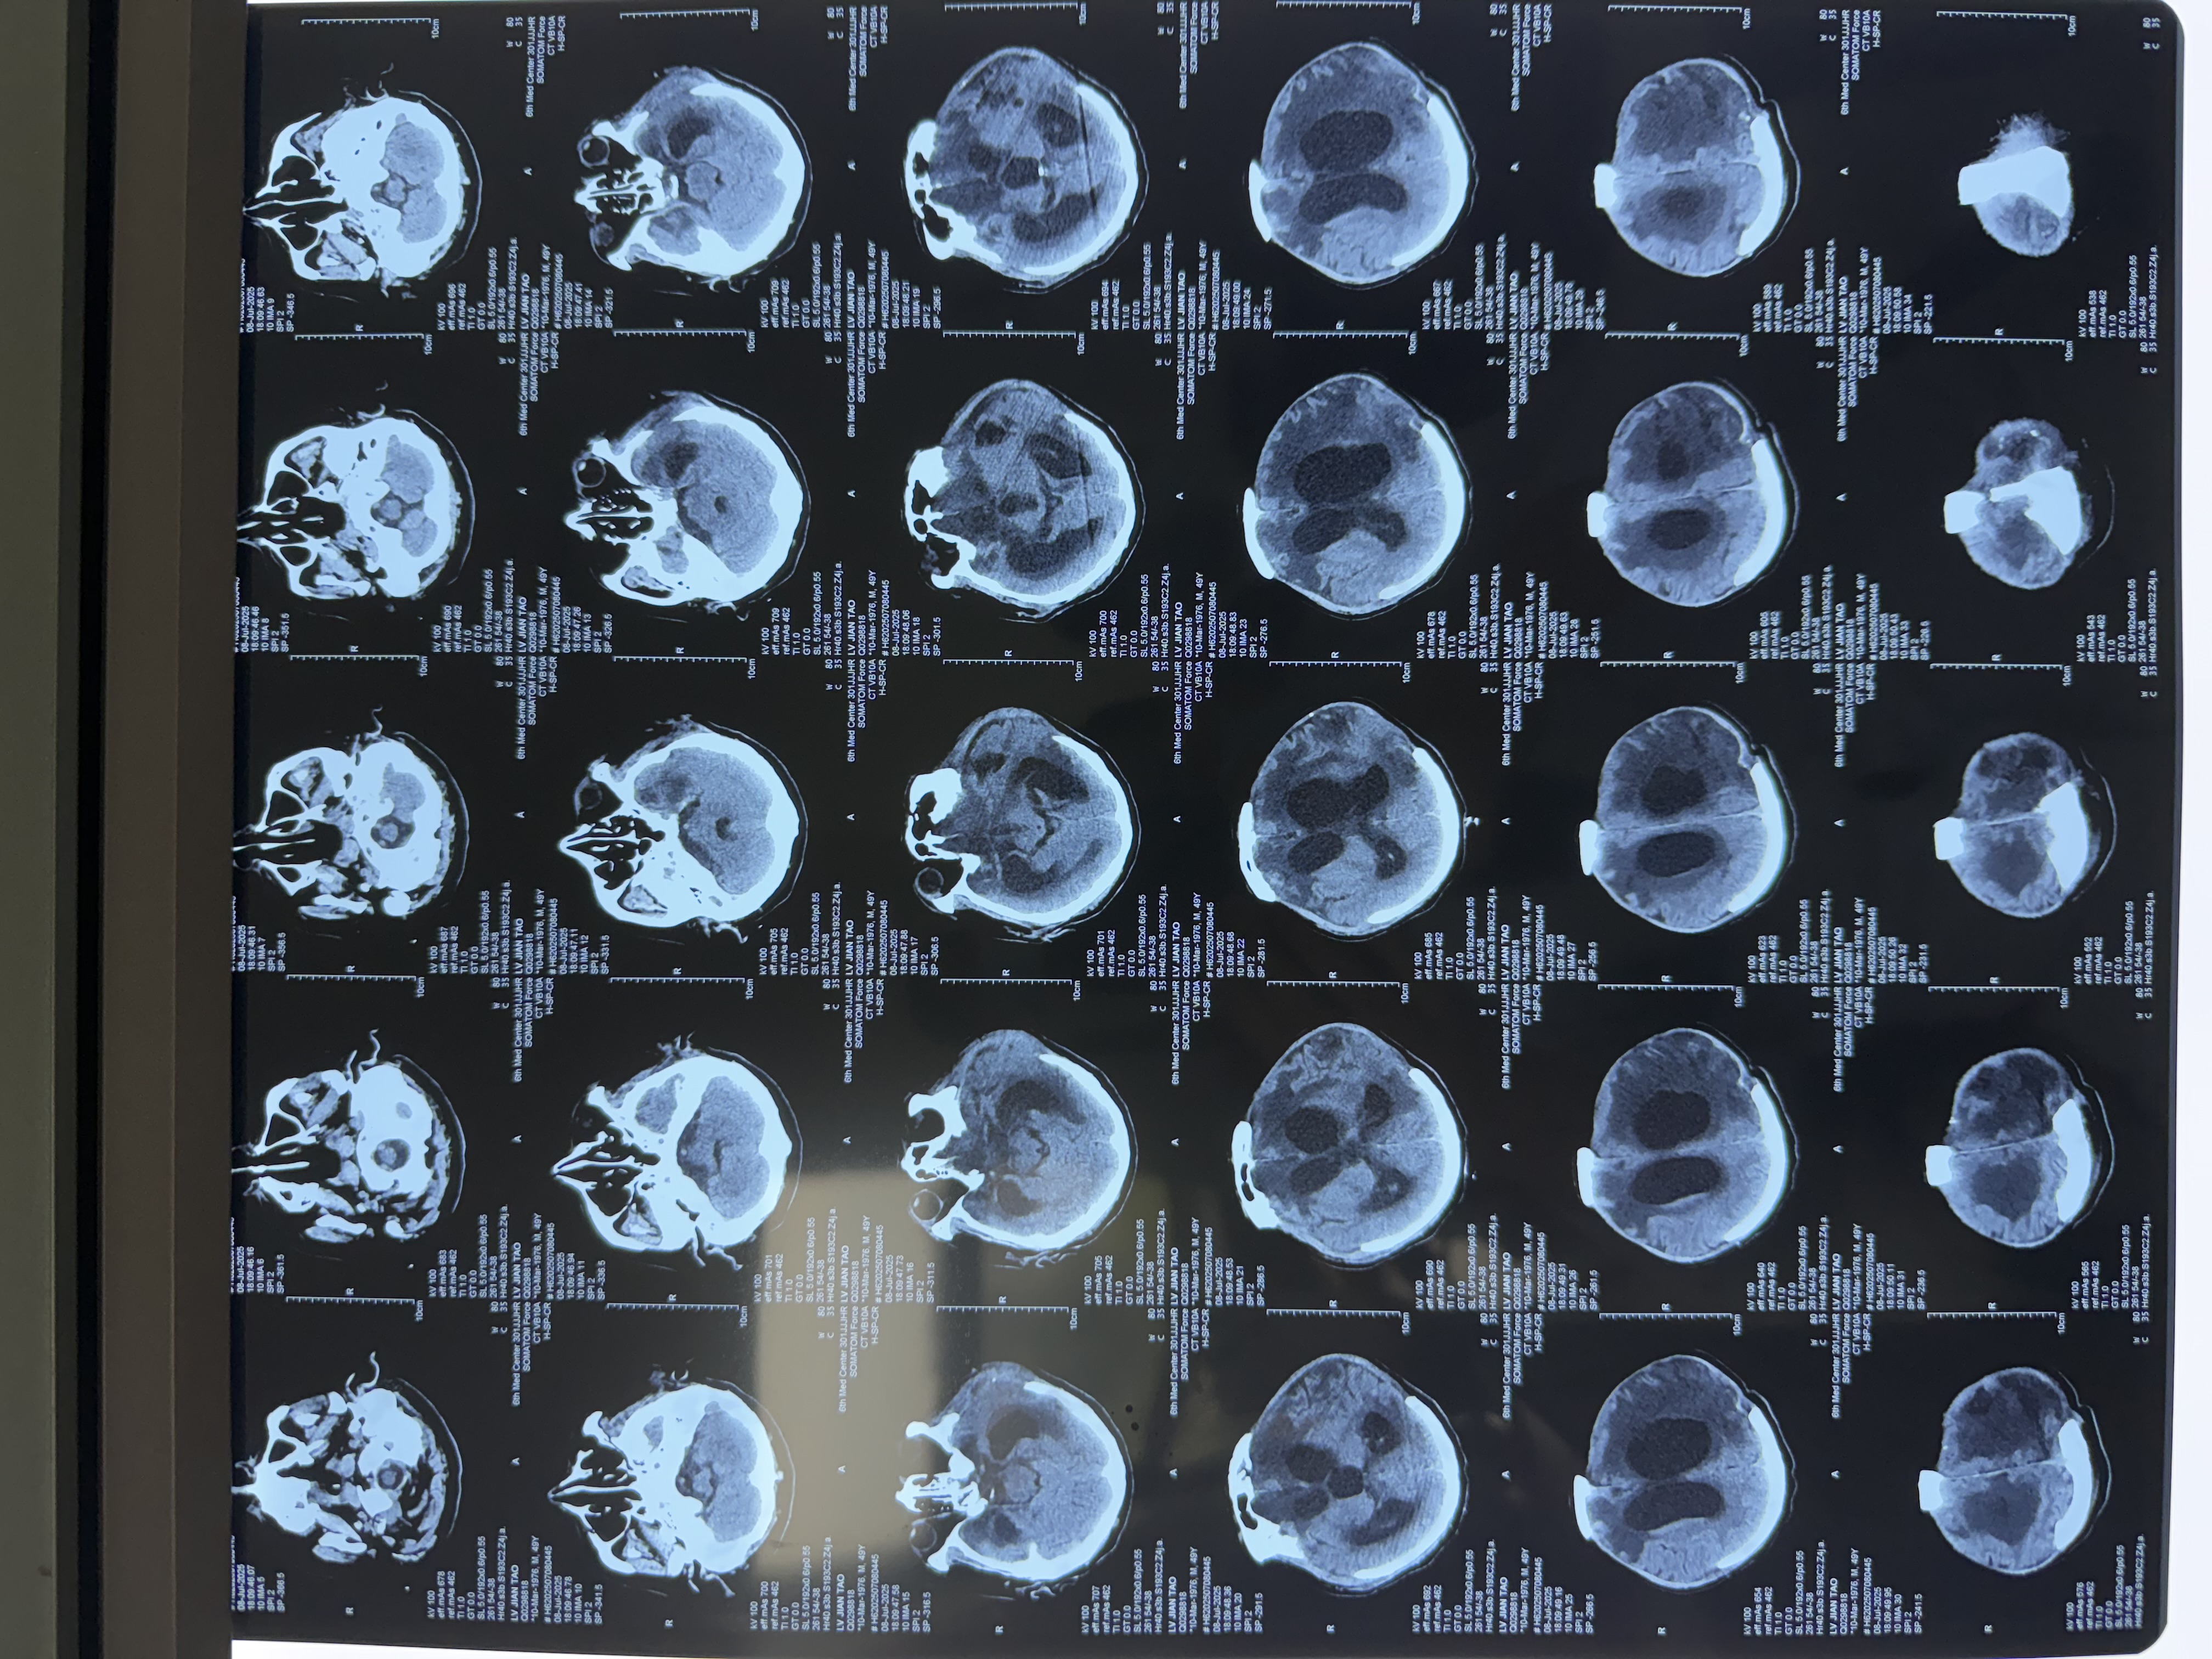

門(mén)診中,常遇到這樣的老人:走路步基寬,容易摔跤;明明記得往事,卻總丟三落四;甚至突然尿急,來(lái)不及上廁所...家人往往以為是“老了”、“帕金森”或“老年癡呆”。但有一種情況,癥狀很像,卻能被手術(shù)逆轉(zhuǎn)!它就是正常顱壓腦積水(NPH)。今天,我們就來(lái)揭開(kāi)它的“隱形面紗”。一、壓力“正?!?,為何傷腦?認(rèn)識(shí)NPH想象一下,大腦里有一套“水管系統(tǒng)”(腦脊液循環(huán)),負(fù)責(zé)滋養(yǎng)和緩沖。當(dāng)這個(gè)系統(tǒng)“堵了”,水排不出去,腦室(大腦里的“水池”)就會(huì)被撐大。關(guān)鍵點(diǎn)來(lái)了:這種堵塞造成的壓力,在常規(guī)測(cè)量時(shí)可能是“正常”的!但這股持續(xù)的壓力,卻在悄悄壓迫腦組織,導(dǎo)致神經(jīng)功能受損,引發(fā)一系列癥狀。高發(fā)人群:60歲以上老人居多,男性稍多。最大誤區(qū):常被誤診為阿爾茨海默?。ɡ夏臧V呆)或帕金森病。最大希望:NPH是少數(shù)可通過(guò)手術(shù)顯著改善甚至逆轉(zhuǎn)的“癡呆”類(lèi)型!二、揪出NPH!三個(gè)警報(bào)信號(hào)最關(guān)鍵NPH有個(gè)“經(jīng)典三件套”,如果家里老人出現(xiàn)以下任何兩個(gè)以上癥狀,務(wù)必提高警惕:1.走路不穩(wěn)像“企鵝”(最核心!):走路時(shí)兩腳分得很開(kāi),像踩在棉花上,步子很小。起步困難,轉(zhuǎn)身時(shí)特別容易搖晃、摔倒。手臂擺動(dòng)正常,不像帕金森那樣僵硬顫抖。家人觀察:是否頻繁摔跤?轉(zhuǎn)身時(shí)特別不穩(wěn)?2.記性變差,但“不太一樣”:不是完全忘記!過(guò)去的事記得清楚,但近期事情容易丟三落四。做事“卡殼”:知道要做什么(比如拿杯子喝水),但動(dòng)作反應(yīng)慢,好像“指揮不動(dòng)”手腳。注意力難集中,計(jì)劃事情變得困難(比如做飯步驟混亂)。家人觀察:是記不清剛發(fā)生的事,還是干脆忘記親人?做事是不是變“笨拙”了?3.憋不住尿,甚至尿褲子:早期可能是尿頻、尿急,總想上廁所。嚴(yán)重時(shí),會(huì)控制不住地尿濕褲子(尿失禁)。家人觀察:是否頻繁上廁所?有沒(méi)有來(lái)不及去廁所弄濕褲子的情況?別只當(dāng)是前列腺問(wèn)題或膀胱炎!提示:這三個(gè)癥狀不一定同時(shí)出現(xiàn),有時(shí)只出現(xiàn)一兩個(gè)。尤其走路不穩(wěn)是最敏感的信號(hào)!千萬(wàn)別簡(jiǎn)單歸咎于“人老了”。三、醫(yī)生如何確診NPH?三步走!如果懷疑是NPH,我們會(huì)進(jìn)行專(zhuān)業(yè)評(píng)估:1.詳細(xì)問(wèn)診:重點(diǎn)了解“三件套”癥狀的特點(diǎn)、出現(xiàn)時(shí)間和變化情況,以及是否有過(guò)腦外傷、腦出血、腦膜炎等病史。2.關(guān)鍵檢查-頭部影像(CT/MRI):這是必做項(xiàng)!我們主要看:腦室是不是變大了?(特別是側(cè)腦室前角像吹脹的氣球)。腦溝(腦表面的皺褶)有沒(méi)有明顯變寬?NPH患者腦溝相對(duì)正常或變淺,這和老年癡呆(腦溝明顯增寬、腦萎縮)完全不同!對(duì)比圖:左圖為AD患者腦溝圖,右圖為NPH患者腦溝圖,3.“放水”試驗(yàn)-腰椎穿刺:這是驗(yàn)證治療是否有效的“金鑰匙”!我們通過(guò)腰穿放出少量腦脊液(30-50ml),觀察48小時(shí)內(nèi):走路是否明顯變穩(wěn)了?反應(yīng)是否變快了?說(shuō)話(huà)、做事是否更利索了?排尿控制是否有改善?如果癥狀有顯著好轉(zhuǎn),就強(qiáng)烈提示是NPH,并且手術(shù)效果會(huì)很好!四、曙光:手術(shù)引流,重獲生活希望!一旦確診,且“放水”試驗(yàn)有效,腦脊液分流手術(shù)是首選治療方案!原理很簡(jiǎn)單:在大腦“水池”(腦室)里放一根細(xì)軟管,把多余的腦脊液引流到腹腔(或心房)吸收掉,解除腦組織的壓迫。效果令人鼓舞:約60%-70%的患者,走路不穩(wěn)明顯改善!約50%的患者,思維反應(yīng)、記性變好!高達(dá)80%的患者,尿失禁問(wèn)題得到緩解或解決!時(shí)機(jī)就是生命線(xiàn):越早手術(shù),效果越好!特別是癥狀出現(xiàn)1年內(nèi),大腦損傷還不太重時(shí)手術(shù),效果最佳。拖得越久(比如超過(guò)3年),恢復(fù)起來(lái)就越困難。五、韓教授給您的實(shí)用提醒:哪些人該警惕?年齡:60歲以上老人風(fēng)險(xiǎn)增加。病史:有過(guò)嚴(yán)重頭部外傷、腦出血(尤其是蛛網(wǎng)膜下腔出血)、腦膜炎的人,更要留心。家人自查(劃重點(diǎn)):?走路不穩(wěn),尤其轉(zhuǎn)身容易摔跤??近期記性變差(丟三落四),但過(guò)去的事記得清??憋不住尿,甚至尿褲子?如果家里長(zhǎng)輩符合≥2條,特別是走路不穩(wěn)+其中任何一條,請(qǐng)務(wù)必盡快帶TA到神經(jīng)內(nèi)科就診!千萬(wàn)別陷入這些誤區(qū):?“人老了,走路慢點(diǎn)、記性差點(diǎn)正常!”?“尿褲子?肯定是前列腺(男)/膀胱松了(女)!”?“癡呆?沒(méi)法治了,認(rèn)命吧...”結(jié)語(yǔ):正常顱壓腦積水(NPH)就像一個(gè)“偽裝者”,癥狀看似常見(jiàn),卻暗藏危機(jī)。但它更是神經(jīng)科醫(yī)生眼中的“希望之星”——因?yàn)樗强勺R(shí)別、可治療的“癡呆”!記住它的“三件套”:企鵝步、特殊健忘、憋不住尿。尤其當(dāng)走路不穩(wěn)成為“主角”時(shí),務(wù)必多留個(gè)心眼。早一天識(shí)別,早一天評(píng)估,早一天手術(shù),就可能幫老人找回穩(wěn)穩(wěn)的步伐、清晰的頭腦和生活的尊嚴(yán)!【轉(zhuǎn)發(fā)提醒家人朋友,別讓“隱形威脅”偷走長(zhǎng)輩健康!】

根據(jù)腦積水的病因,可分為交通性腦積水和梗阻性腦積水,前者與腦積水吸收障礙有關(guān),后者則是由于腦脊液循環(huán)通路受阻所致。本病例為學(xué)齡期女性,因“小腦腫物,梗阻性腦積水”在外院行手術(shù)切除腫瘤后,梗阻性腦積水未能緩解,導(dǎo)致患者劇烈頭痛,嘔吐。我們采用了腦室鏡下第三腦室底造瘺術(shù)對(duì)其進(jìn)行治療,術(shù)后患者頭痛、嘔吐等癥狀完全緩解,術(shù)后5天出院。第三腦室底造瘺術(shù)(ETV)相比于腦室腹腔分流術(shù)具有很多優(yōu)點(diǎn):費(fèi)用低,微創(chuàng),無(wú)異物植入,遠(yuǎn)期并發(fā)癥少等,對(duì)于符合造瘺手術(shù)的患者及家屬而言,是給巨大的福音!

復(fù)發(fā)腦積水的診斷